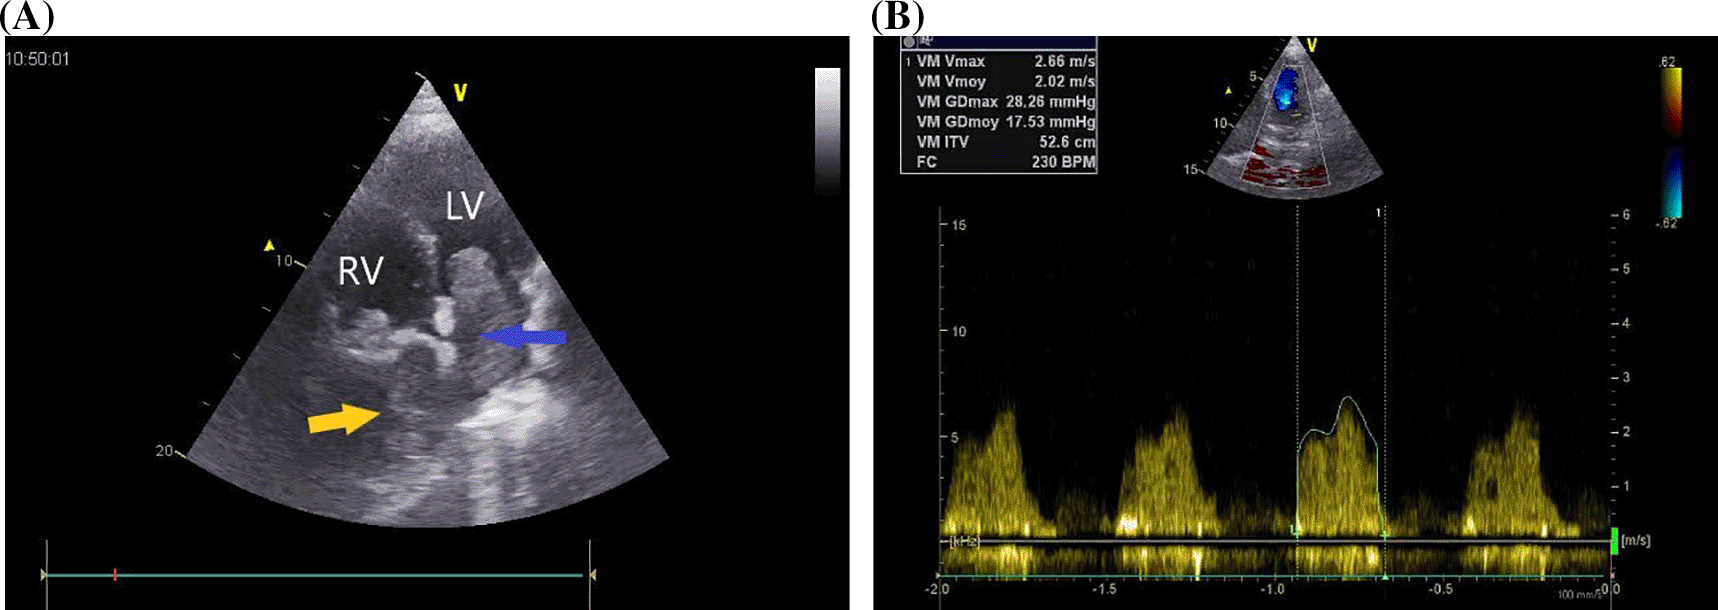

A 37-year-old Maghrebian female patient was presented to the cardiology department due to complaints of dyspnea, progressing over one month. She had a dry cough and had been resistant to symptomatic treatment. The patient was diagnosed with borderline breast PTs ten years earlier, which was treated by surgical excision. Upon examination, her dyspnea was classified as class IV on the New York Heart Association Functional Classification with orthopnea. Her transcutaneous oxygen saturation was 92%, and pulmonary auscultation revealed bibasilar crackles. Additionally, the patient’s chest x-ray showed a homogeneous opacity located in the basal part of the right lung. Transthoracic echocardiography (TTE) revealed 5 × 4 cm homogenous mass occupying nearly all the left atrium (LA), resulting in severe mitral valve obstruction (mean gradient = 17 mmHg) (Figure 1).

LV: left ventricle, MV: mitral valve, RV: right ventricle.

A second huge mass compressed the right atrium posterior wall. Following respiratory stabilization, transesophageal echocardiography confirmed TTE results and revealed an extended mass into LA via the right inferior pulmonary vein (RIPV) (Figure 2). Cardiac computed tomography (CT) revealed a large (100 × 70 × 100) mediastino-pulmonary mass extending to LA via RIPV (Figure 3).